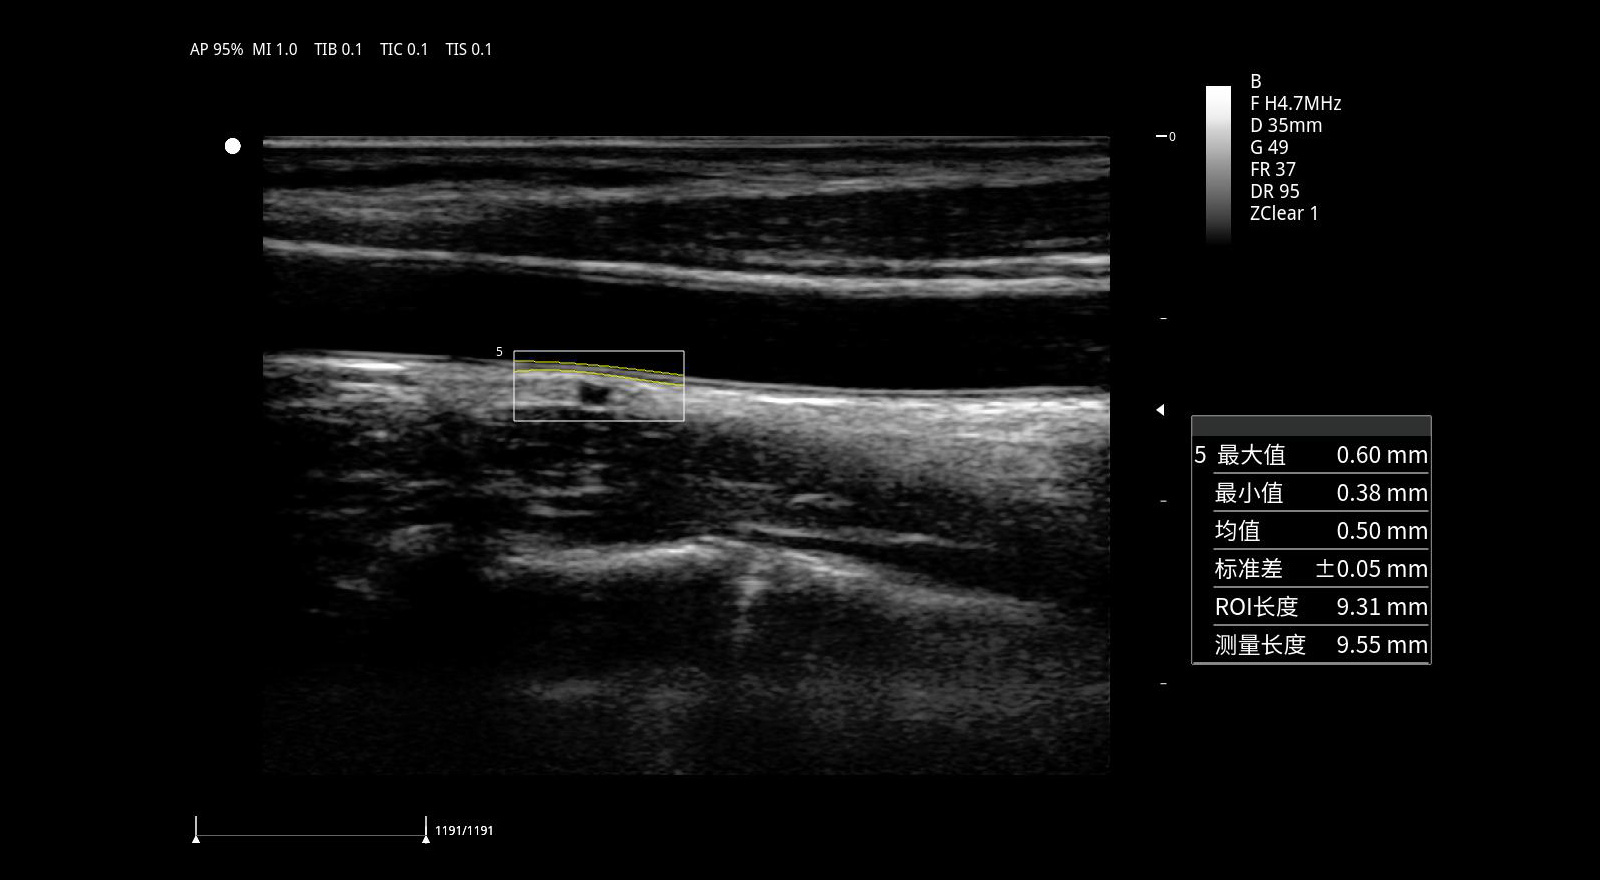

Medición automática del espesor íntima-media. IMT.

Con IMT, se puede detectar y medir automáticamente el espesor de la íntima-media y se puede generar un informe de espesor de la íntima-media, lo que proporciona predictores independientes para la prevención de eventos cardiovasculares.

Medición automática del espesor íntima-media (IMT): Detección y medición automática del IMT con informe completo, útil en prevención cardiovascular.

Optimización en estudios cardiovasculares mediante medición automática de IMT.